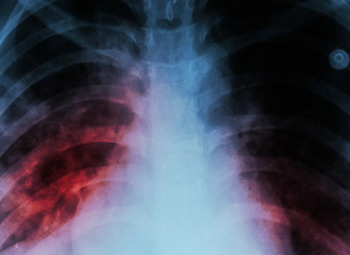

Mortes por tuberculose aumentaram na Europa

É o primeiro aumento de óbitos registado em mais de duas décadas.

Leia MaisA tuberculose é uma doença infectocontagiosa de grande prevalência no Brasil. Boletins divulgados recentemente mostram o panorama atual da doença no país, tanto em relação ao número geral de casos quanto a casos de multirresistência